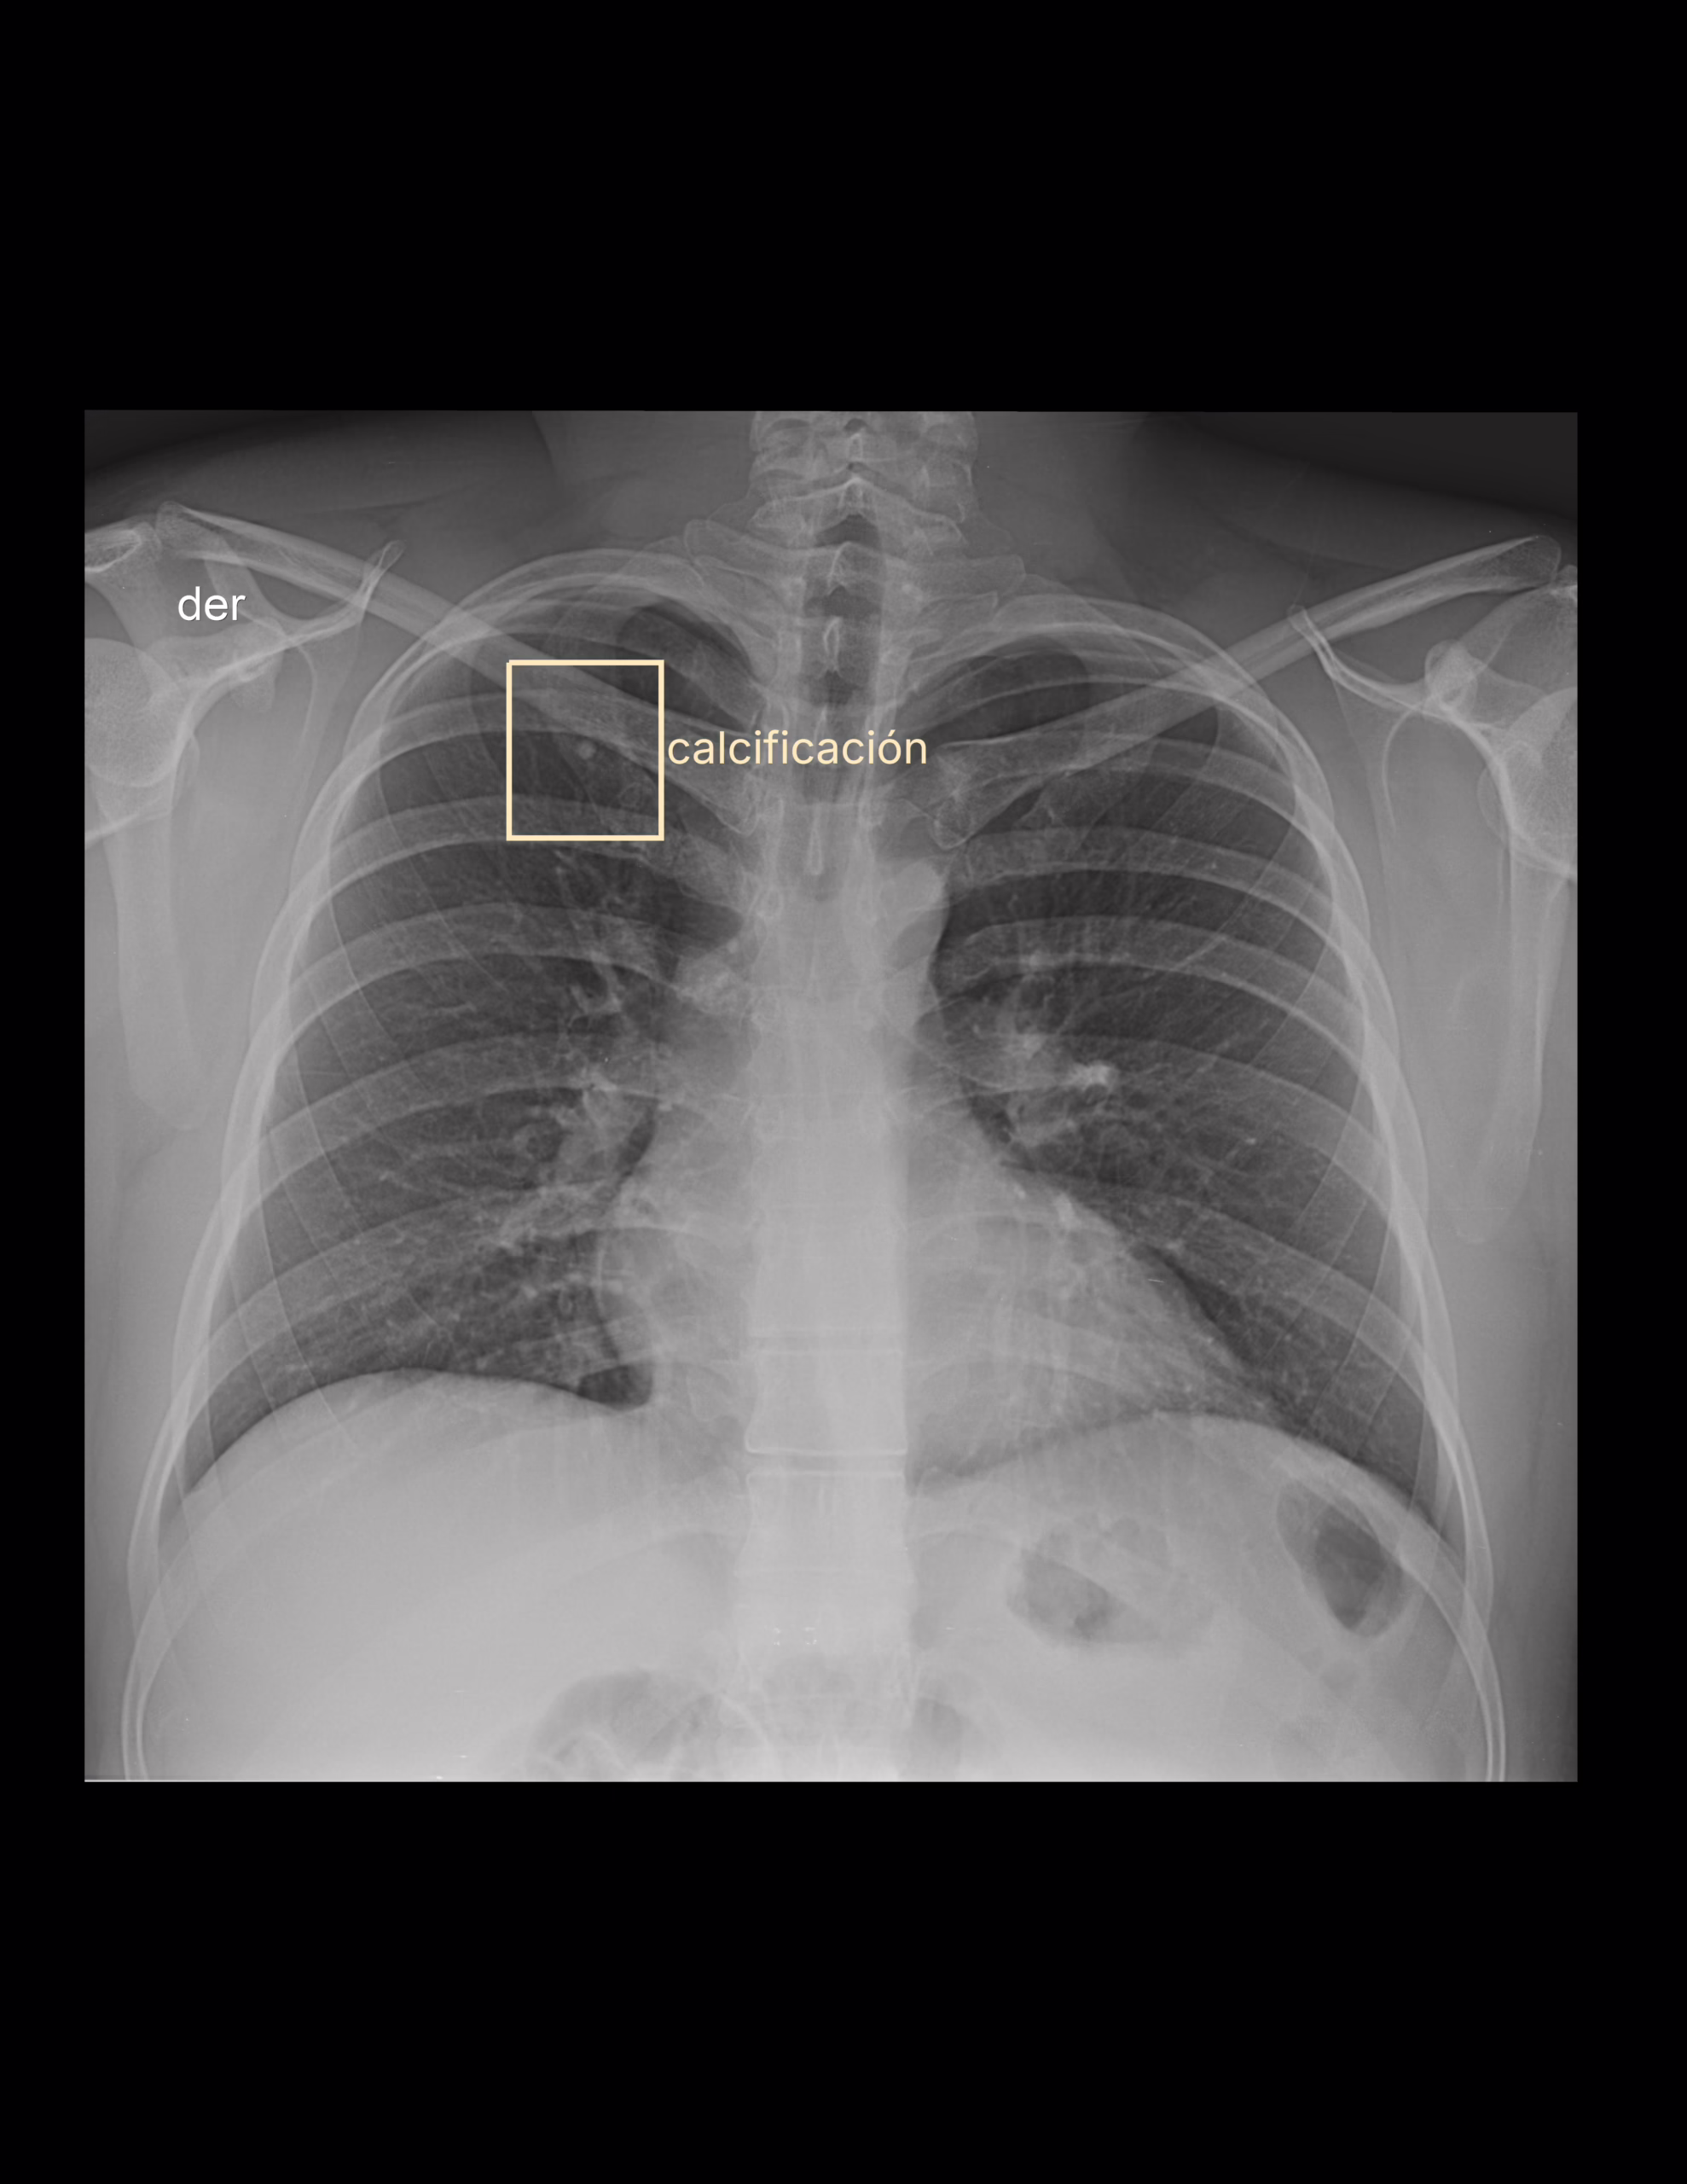

Imagen radiopaca proyectada en el primer arco costal derecho de 4.5 mm. que sugiere granuloma pulmonar calcificado.